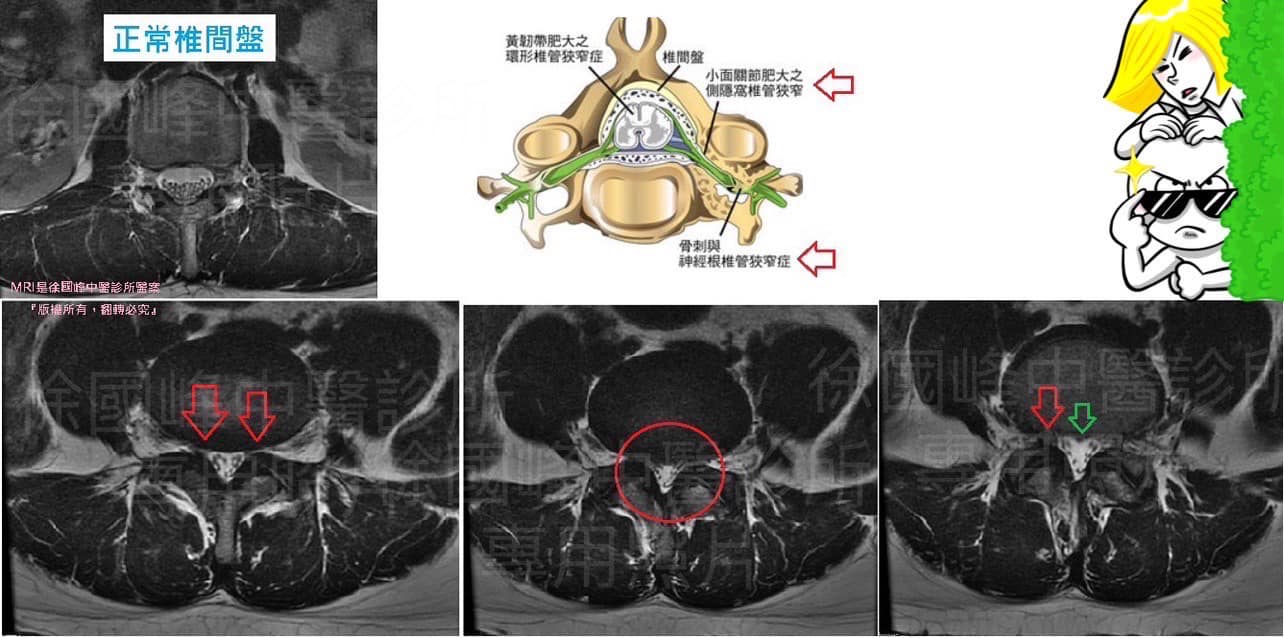

🔴醫師如何診斷出腰椎管狹窄症

1️⃣病歷:腿部疼痛,並有機會背部同時出現疼痛。

2️⃣檢查:通常是背部僵硬,身體其他部份亦可能有病癥。

3️⃣腰椎X光片- X光片往往能顯示退化的轉變,屈曲及伸展的X光片可顯示出脊柱的活動是否不正常。

4️⃣核磁共振掃描 (MRI) - 核磁共振掃描對於評估脊椎的問題非常有用,因為它能顯示出神經、其他軟組織和骨骼。